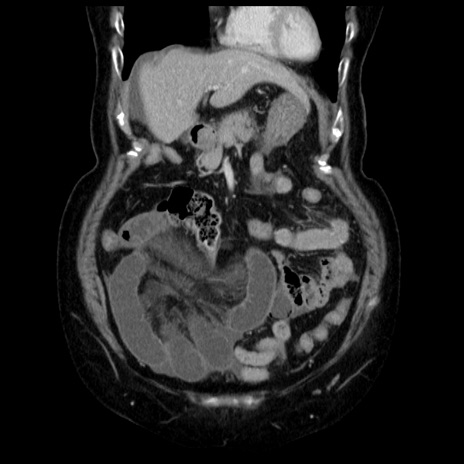

症例13(冠状断像)

【症例】70歳代女性

【主訴】腹痛、嘔吐

【現病歴】15時間程前(昨晩)より腹痛あり。今朝になっても症状の改善なく、嘔吐あり。腹痛も増悪あり、救急外来受診。

【既往歴】子宮癌全摘術後

【身体所見】意識清明、BP 121/72mmHg、P 74bpm、SpO2 100%(RA)、腹部:平坦・軟、腸雑音ほぼ聴取せず。下腹部・心窩部・臍左上に圧痛あり。反跳痛なし。

【データ】WBC 10600、CRP 0.15